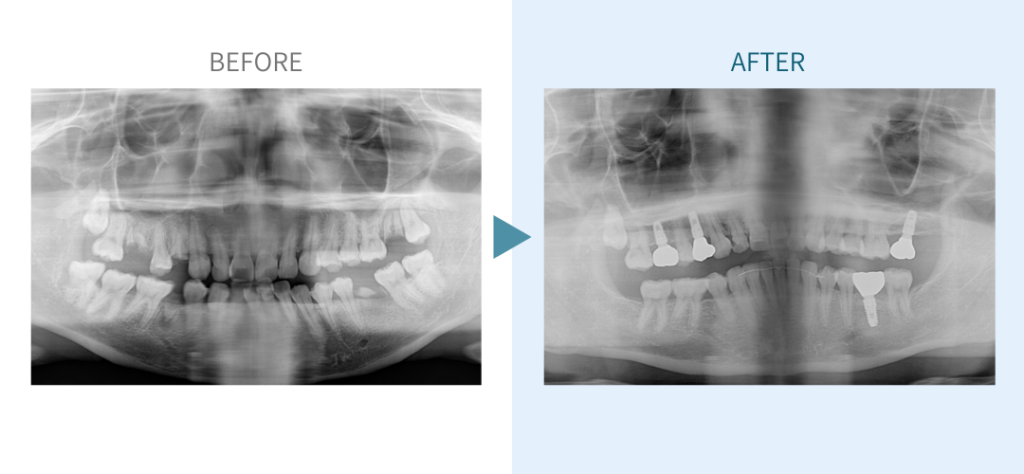

デンタルチームジャパンでは、サイナスリフト(上顎洞底挙上術)や骨造成など、他院で「骨が足りない」と断られた難症例にも対応しています。

私たちは、難症例に関する治療法を学会でも発表しており、その豊富な実績と技術力が評価され、全国から患者様が来院いただいております。

こちらではその一部の症例についてご紹介します。